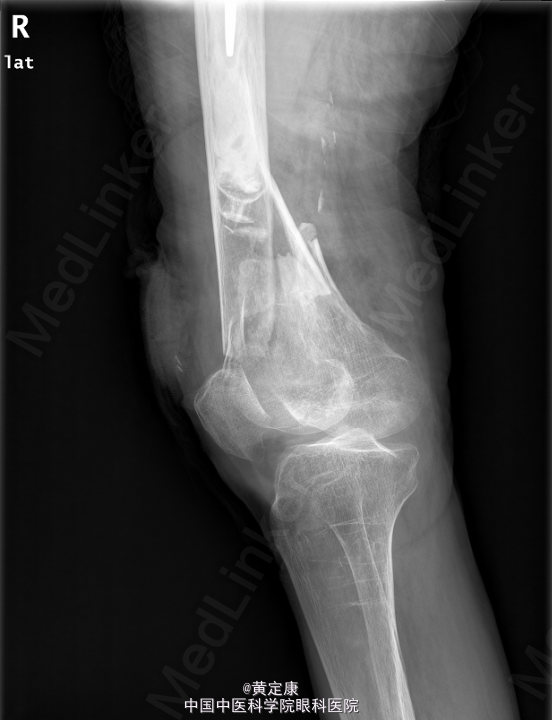

患者,女,82岁,因“摔伤致右下肢疼痛伴功能受限1天”入院。 患者1天前因外伤致右下肢剧烈疼痛,无法行走,。送至外院急诊,X线示“右股骨髁上骨折”,拟“右股骨髁上骨折”收治入院。

右膝部肿胀,膝关节活动受限,右足各趾活动感觉正常,末梢血运正常。石膏固定。检查提示:右股骨髁上骨折。

初步诊断: 右股骨髁上骨折 行[右]股骨骨折切开复位钢板内固定术